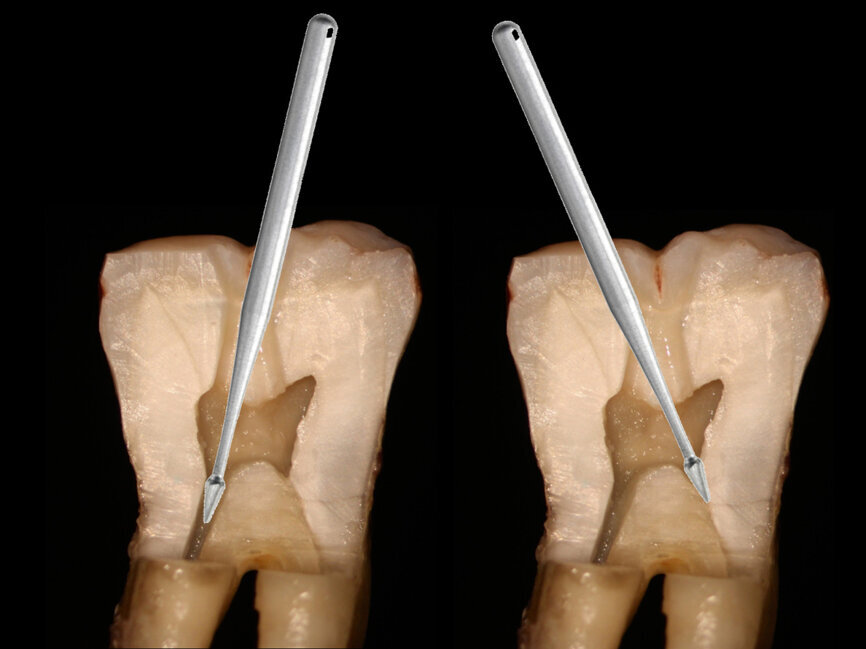

Fig. 5: In anterior teeth, the canal orifice is typically located just lingual to the incisal edge in incisors and the cusp tip in canines (middle) or directly under the incisal edge or cusp tip (right).

Fig. 6: A potential problem when attempting to access the orifice in anterior teeth is an approach at the middle of the lingual surface with an angle not following the root’s long axis that can lead to perforation of the tooth on the facial cervical (A), and the bur being used for access should be kept parallel to the roots long axis which often places the orifice under the incisal edge (B).

Anterior teeth, whether maxillary or mandibular, can pose some potential challenges when the practitioner does not understand the tooth’s anatomy in relation to the canal and its orifice. When an anterior tooth is viewed laterally from the proximal, the canal following a straight axis places the canal orifice either directly under the incisal edge or slightly lingual to the incisal edge for incisors (Fig. 5). Canines will typically have the canal orifice directly under the cusp tip, and this should be kept in mind when treating those teeth. A frequent approach in anterior teeth is to initiate access in the middle of the lingual surface, which can place the access too lingual to where the orifice actually lies. Additionally, if the bur is not held parallel to the tooth’s long axis of the root it is possible in attempting to locate the pulp chamber the bur may perforate the tooth on the facial cervical, creating additional treatment problems (Fig. 6). Use of a long shaft bur such as the Endoguide makes paralleling the tooth’s long axis easier then with standard-length burs.